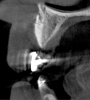

Fig 10. Tomographic images of teeth Nos. 6 (Fig 10), 7 (Fig 11), and 8 (Fig 12) clearly showed vertical gains in alveolar height, including in the edentulous area corresponding to tooth No. 7. The apex of tooth No. 8 was located within the soft tissue because it was force-erupted beyond its socket.

Figure 10

Fig 11. Tomographic images of teeth Nos. 6 (Fig 10), 7 (Fig 11), and 8 (Fig 12) clearly showed vertical gains in alveolar height, including in the edentulous area corresponding to tooth No. 7. The apex of tooth No. 8 was located within the soft tissue because it was force-erupted beyond its socket.

Figure 11

Fig 12. Tomographic images of teeth Nos. 6 (Fig 10), 7 (Fig 11), and 8 (Fig 12) clearly showed vertical gains in alveolar height, including in the edentulous area corresponding to tooth No. 7. The apex of tooth No. 8 was located within the soft tissue because it was force-erupted beyond its socket.

Figure 12

After 3 months of post-orthodontic stabilization, a cone-beam computed tomography scan was taken to re-evaluate the results and plan the future treatment sequence. Tomographic images clearly showed vertical gains in alveolar height, including in the edentulous area corresponding to tooth No. 7 (Figure 10 through Figure 12). The apex of tooth No. 8 was forced-erupted beyond its socket and could be visibly located within the soft tissue.30,33